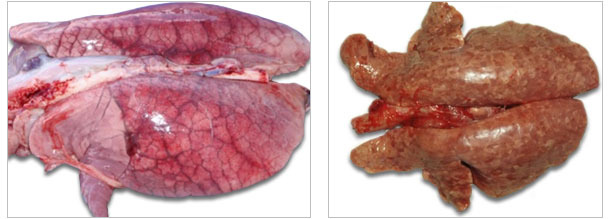

| Ostry obrzęk płuc niekiedy obserwowany w przebiegu ostrego PCVAD. | Ciemne i tęgie płuca (zapalenie śródmiąższowe) świni zakażonej PCV2. |